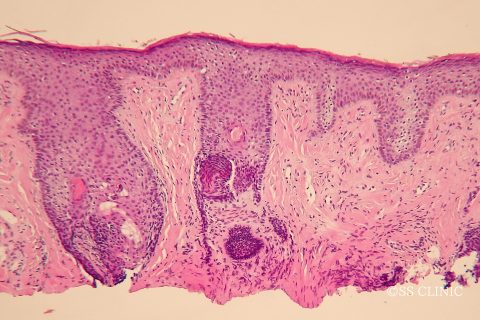

病理組織はfibrous papule(線維性丘疹)です。